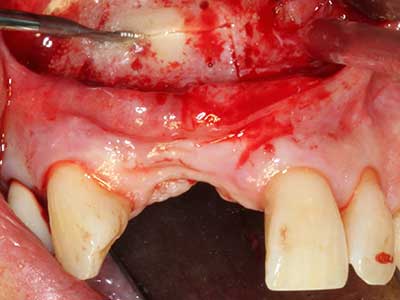

Фиг. 18: Препарация на кортикално покритие с пиезо накрайник за кост (Piezomed, W&H).

Фиг. 19: Хирургичното поле след невролиза и отстраняване на остеотом.

Фиг. 20: Отстраненото костно покритие е поставен отново и фиксиран с винт за остеосинтеза (KLS Martin, Tuttlingen).